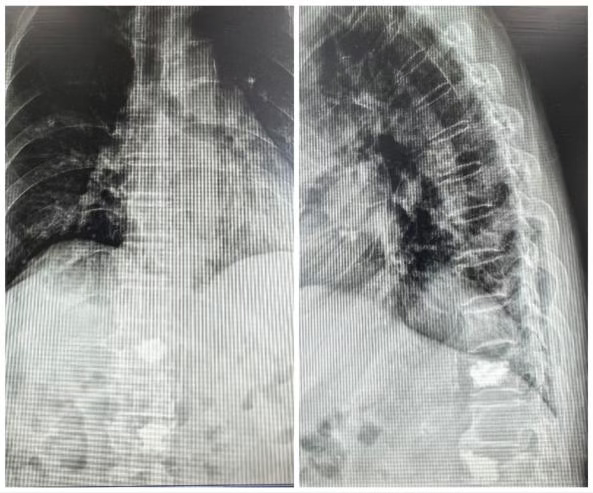

据了解,这名百岁老人因不慎跌倒导致胸11椎体压缩性骨折,剧烈的疼痛让老人无法坐起,只能卧床。传统的保守治疗需要长期卧床,不仅会因疼痛过程漫长严重影响患者的生存质量,还极易引发肺部感染、压疮、下肢静脉血栓等严重并发症,甚至危及生命。然而,为如此高龄的患者进行手术治疗,麻醉和手术本身的风险都极高。加之患者本身伴有慢阻肺、高血压、冠心病等基础疾病,对患者的风险管控是我院专家团队面对的巨大考验。

入院时影像

手术前后对比

该手术仅通过背部几毫米的微小切口,在影像引导下,将特制的球囊置入被压扁的椎体内,通过扩张球囊将椎体复位、撑起,然后注入骨水泥,迅速稳定骨折椎体。整个过程创伤极小、出血少、时间短,适合高龄、体弱、无法耐受常规开放手术的患者。手术仅历时25分钟,术后效果显著,患者原本难以忍受的疼痛感已基本消失。